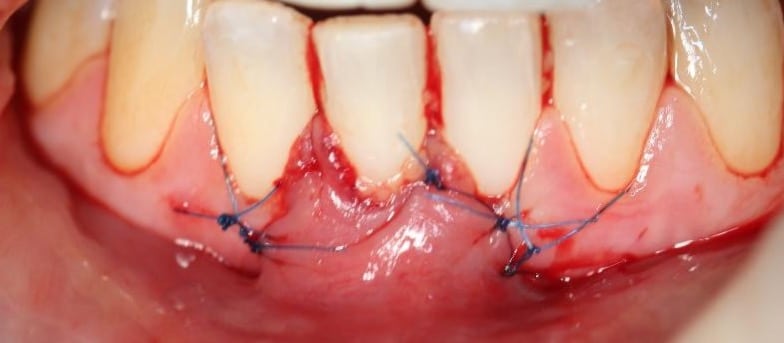

Coronally Advanced Flap with connective tissue graft

This method is commonly used to achieve total root coverage in isolated and multiple recession sites. This method requires harvesting a connective tissue graft from the palate. This graft is then sutured onto the defect, and it is subsequently covered by a coronally advanced flap.

Figure 2. Surgical management of lower anterior recession using a coronally advanced flap and subepithelial connective tissue graft.